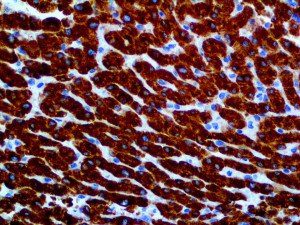

It is the ICU physician who is most likely to witness one of the deadliest manifestations of the abnormal immunological response, the cytokine storm syndrome (CSS). This response is also referred to by some as the cytokine release syndrome (CRS). CSS is characterized by continuous activation and expansion of macrophage and lymphocyte populations, which secrete large amounts of cytokines, causing the cytokine storm. This massive cytokine release is akin to hemophagocytic lymphohistiocytosis (HLH) disease, a syndrome characterized by initial unchecked and persistent activation of cytotoxic T lymphocytes and NK cells.

Clinical and laboratory manifestations of HLH include fever, enlarged liver and/or spleen, neurologic dysfunction, coagulopathy, liver dysfunction, cytopenias (i.e., low levels of erythrocytes, leukocytes, and/or platelets), hypertriglyceridemia, hyperferritinemia, hemophagocytosis, and eventually diminished NK cell activity as the immune system becomes progressively paralyzed. HLH can be familial (primary HLH) or secondary to another disease process (sHLH), such as rheumatic disease, in which it is referred to as macrophage activation syndrome (MAS, characterized by elevated ferritin).